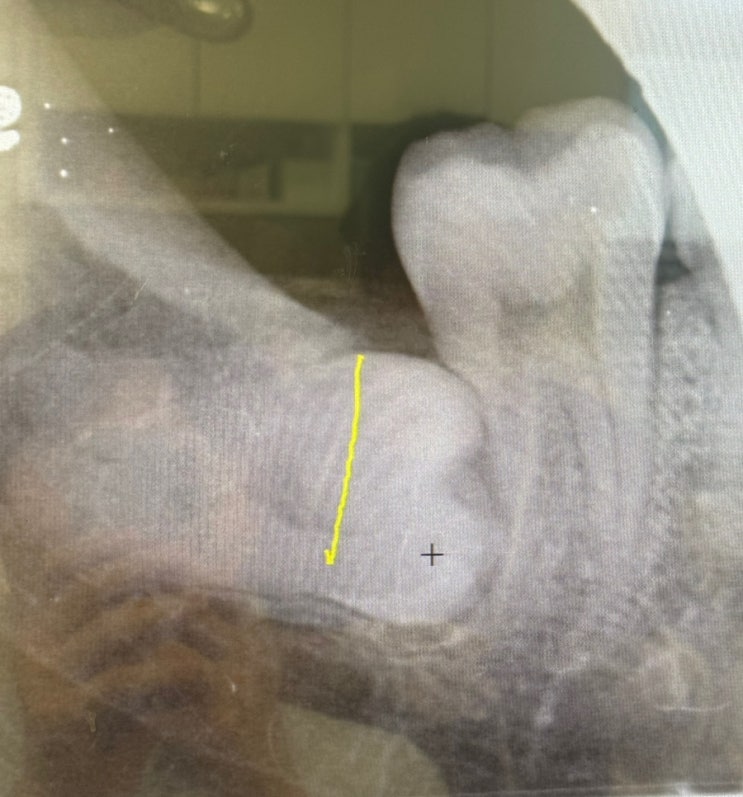

사랑니 발치 하치조신경손상 기록 #1(16일 ~ 2달)

#하치조 신경마비 16일차 ~ 2달차 기록. 2024.02.20. 매복사랑니 발치과정에서 치아뿌리가 하치조신경을 누...

사랑니 발치 하치조신경손상 기록 #1(발치직후 ~ 15일)

1. 우측 하악 매복사랑니 발치 - 2024.02.20.(화) - 발치 진행 배경: 평소 오른쪽 아래 어금니쪽에 이름모...